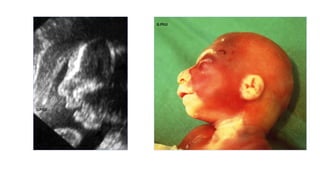

MICROCEPHALY

G.MALINGER G.MALINGER

G.PILU

24ss

TRANSTORNOS DE PROLIFERACIÓN:MICROCEFALIA • Antenatally is even more difficult, because affected fetuses have usually normal cranial measurements in early gestation, that only decline in late gestation or after birth. • The incidence is estimated to be 1.6 per 1000 singlebirth deliveries. Only 14 % of all microcephalic infants diagnosed by the first year of age had been detected at birth. • The available literature suggests that the risk of mental retardation with an head circumference between – 2 and – 3 SDs is in the range of 10-30%, rising to 50-60% for measurements below – 3 SDs.